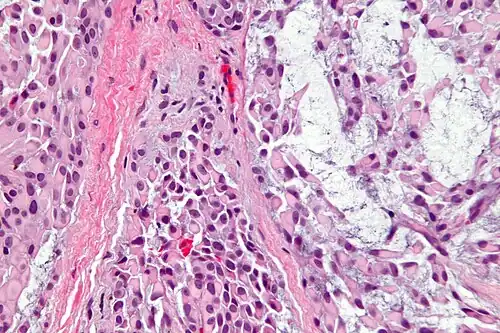

Histologicamente, é caracterizado por ser predominantemente (>95%) composto por células mioepiteliais, sejam elas de características fusiforme, epitelioide, plasmocitoide, claras ou oncocíticas.[1][5] São bem delimitados ou até mesmo encapsulados, e o estroma tumoral, quando presente, pode ser fibroso, hialinizado, mixoide ou mucinoso, raramente tendo aspecto lipomatoso.[1] A arquitetura tecidual pode ser dividida em algumas formas: sólida; mixoide; reticular (ou canalicular); ou uma mistura de mais de uma forma, sem diferenciação ductal.[1]